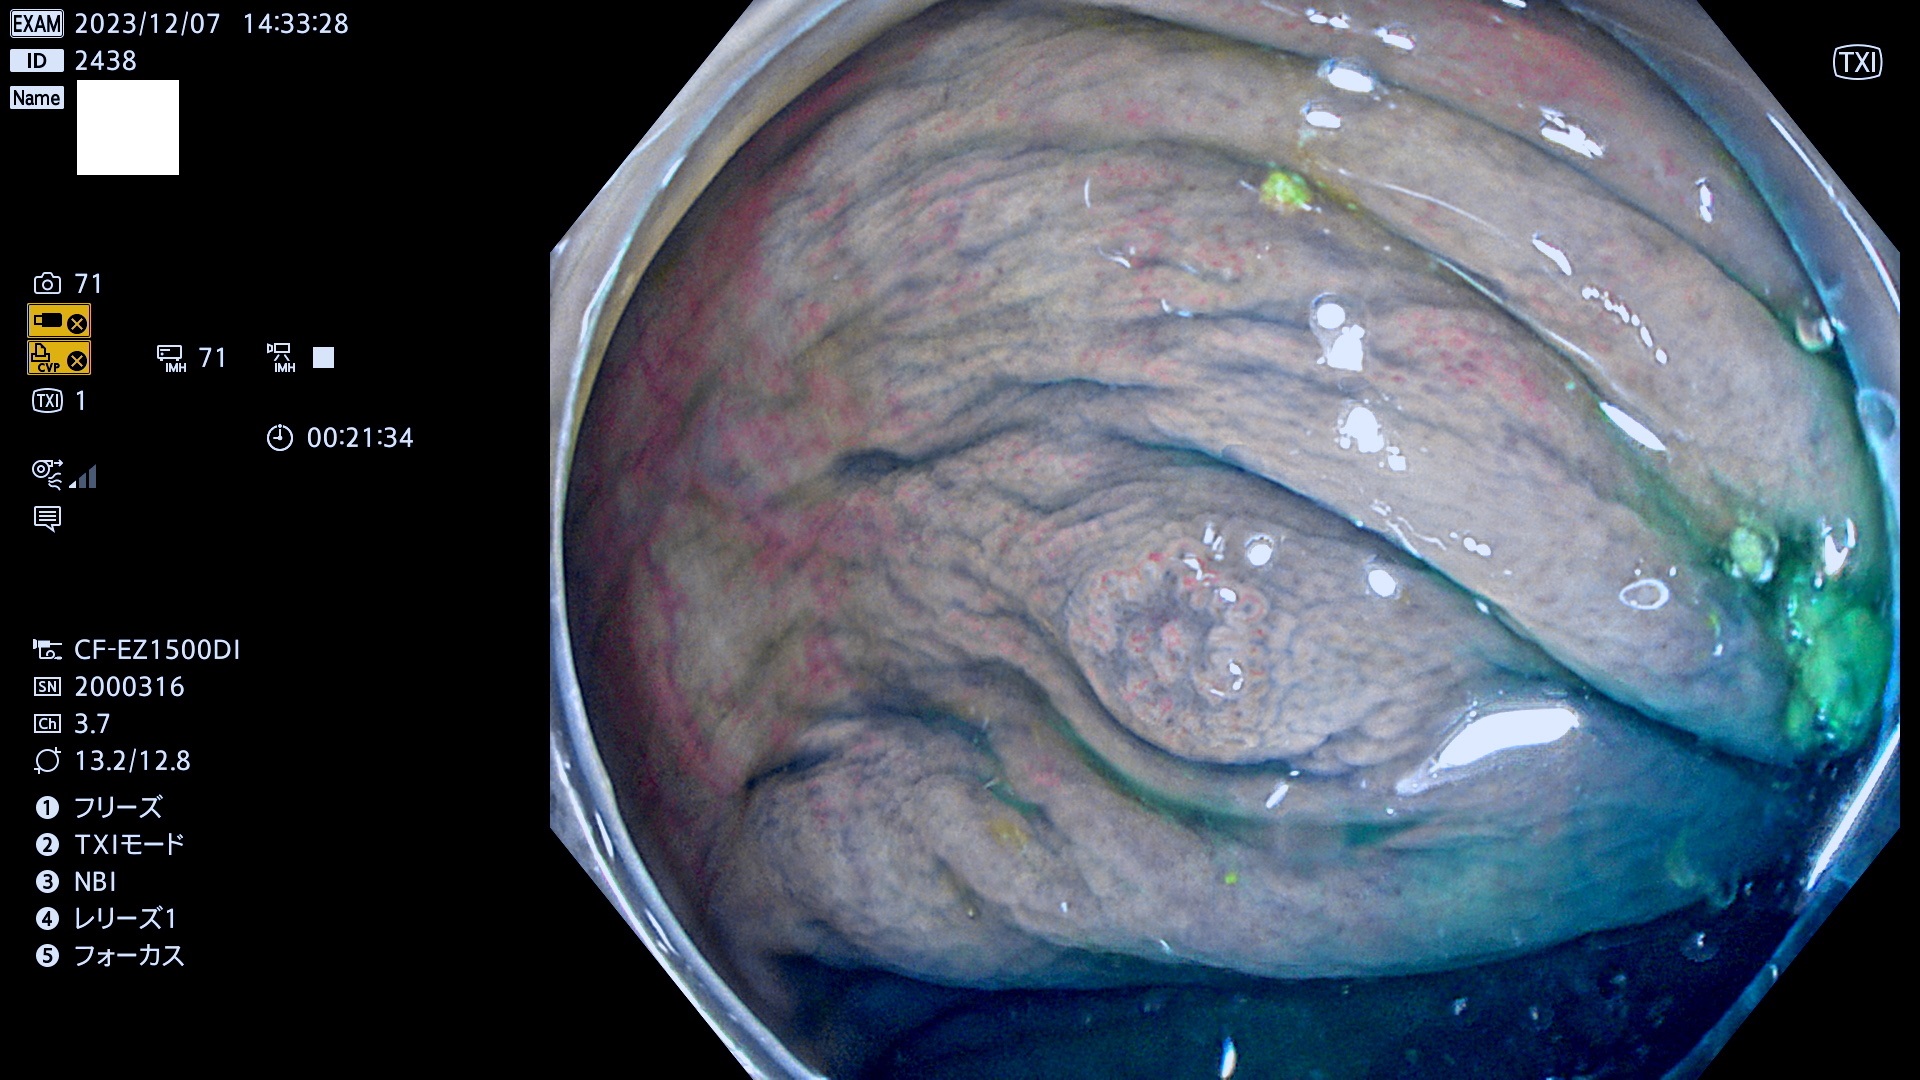

表面型腺腫(Flat Adenoma)の中で、完全に平坦な物をUb、陥凹している物をUcと呼びます。平坦隆起型(Ua)よりも、発見が難しく危険な病変です。このタイプは「内視鏡後・大腸癌の重要犯人」であり、この発見率は「腺腫発見率」よりも、重要な意味があります。

毎週の検査(木・金・土・日)に発見されたUb、Uc型・腺腫を、その週の日曜の夜にUPし1週間、提示します。

抽出の対象期間 2023年12月7日(木)〜12月10(日)の4日間(48件の検査)12件

上記と同一病変